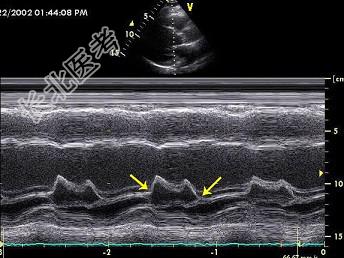

- 单项选择题二尖瓣M型超声心动图,图中箭头所示两点分别称为 ( )

A、E点和A点

B、D点和C点

C、F点和G点

D、高点和底点

E、前点和后点